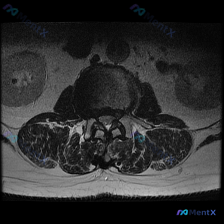

看到这张腰椎MRI T2轴位片,整理一下完整的分析思路分享给大家。

这是一例腰椎MRI T2序列轴位影像,定位为下腰椎节段(L4/5或L5/S1,需结合矢状位确认),影像清晰显示椎体、椎间盘、椎管、硬膜囊、马尾神经、黄韧带、双侧关节突关节及椎旁肌肉结构。

- 椎间盘改变:椎间盘T2呈明显低信号,提示椎间盘脱水退变;椎间盘后缘形态异常,向后方局限性突出,为中央型至左侧旁中央型突出,突出物压迫硬膜囊前方。

- 神经受压改变:椎间盘突出占据椎管前方空间,硬膜囊受压变形,前方蛛网膜下腔间隙消失;突出位于中央偏左侧,导致左侧侧隐窝明显变窄,对左侧神经根造成直接挤压,马尾神经束显示受限。

- 其他结构退变:双侧黄韧带存在一定程度肥厚,双侧关节突关节面不平整,关节间隙狭窄,边缘增生,提示关节突骨关节炎性退变。

- 椎管整体改变:受椎间盘突出、黄韧带肥厚、关节突增生共同影响,椎管呈明显继发性狭窄,硬膜囊受到明确压迫。